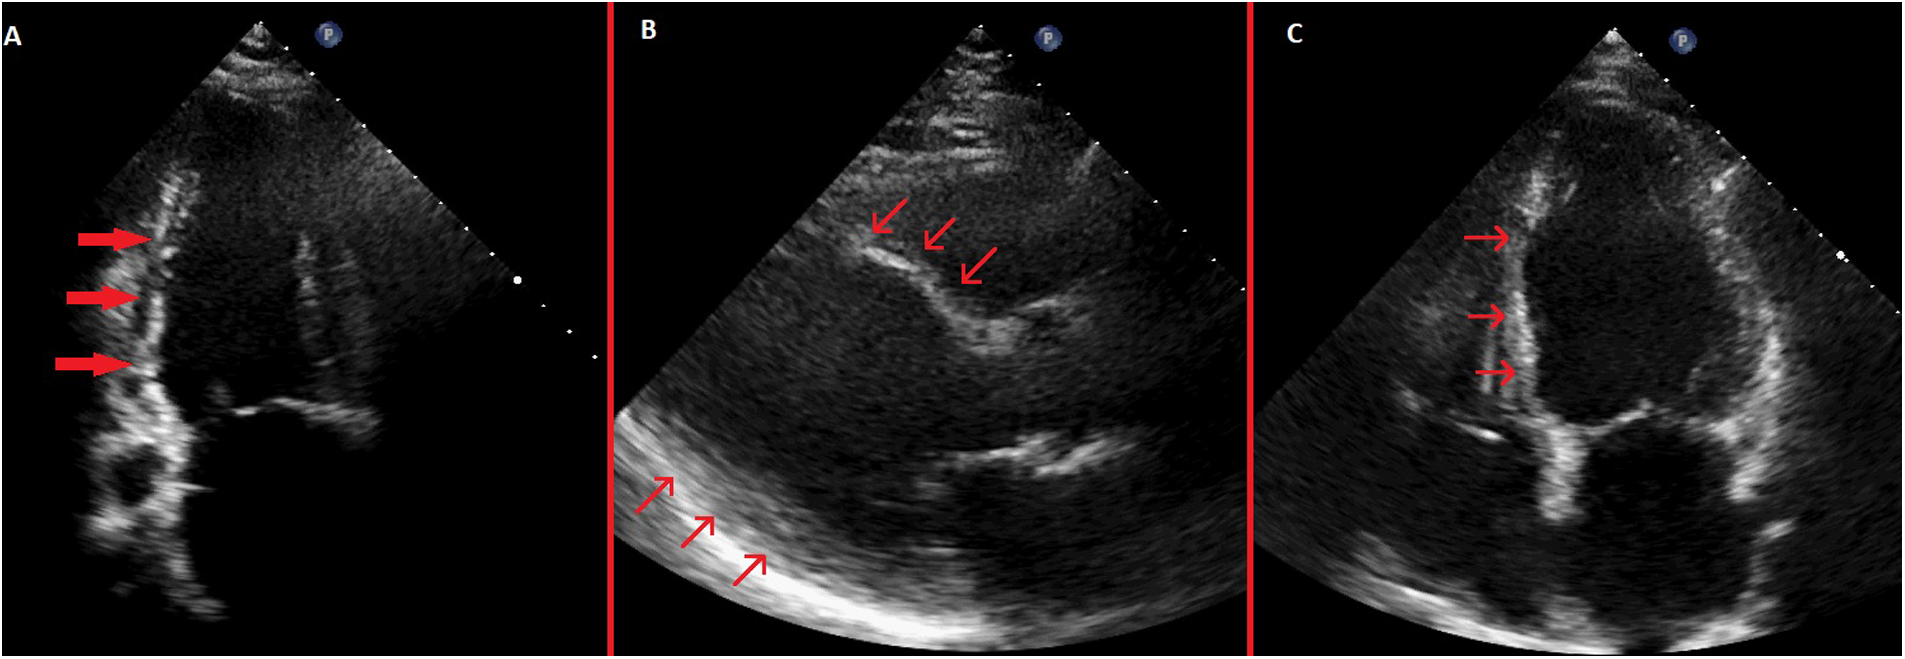

Figure 4

Pre-discharge transthoracic echocardiography images. (A) Systolic apical 2-chamber view showing severe hypokinesis of the inferior wall with thinning of the inferior wall myocardium. (B) Systolic parasternal long-axis view showing akinetic and thinned anterior septum and inferolateral wall hypokinesis. (C) Systolic apical 4-chamber view showing akinetic and thinned basal and mid septum.